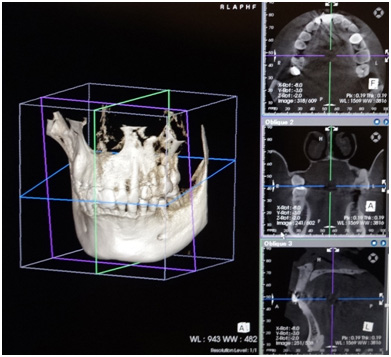

インプラントの手術において最も重要といえるのは診断です。あごの骨の状態をしっかりと把握しておくことが安全な手術に繋がってきます。

従来のレントゲン写真(平面)では診察することのできない血管や神経の位置を正確に把握するためには、3次元のレントゲン(3DCT)での撮影が必須となります。

当院では院内に3DCTを設置する事により、術後にもその場で問題が起きてないかの確認ができるため、より安全にインプラントの手術ができるようになっております

。